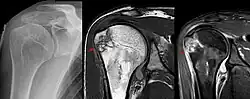

Magnetresonanztomographie

Die Magnetresonanztomographie ist in der Lage, sehr sensitiv ein Ödem des Knochenmarks darzustellen. Da bei praktisch jedem frischen Knochenbruch ein solches Ödem entsteht, kann man so auch dann eine Verletzung des Knochens erkennen, wenn die mineralischen Knochenbälkchen, also das, was in der Röntgenaufnahme dargestellt wird, nicht durch einen Bruch unterbrochen oder verschoben sind.